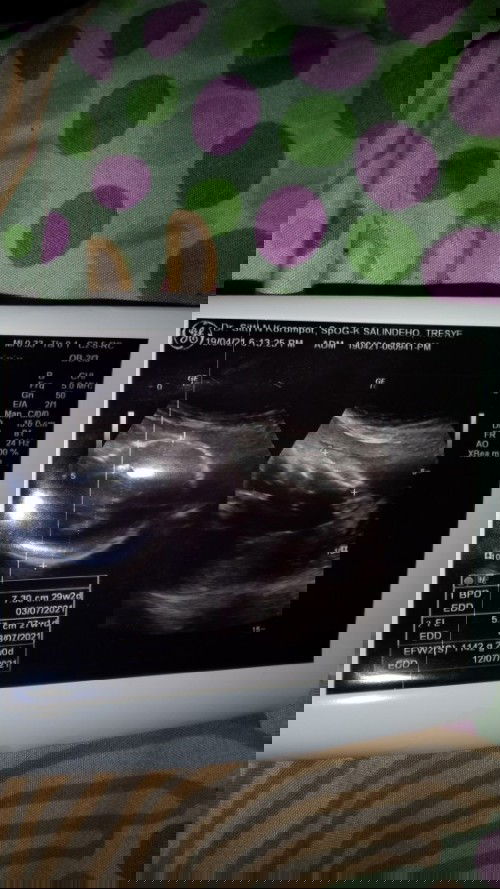

Cara Membaca hasil usg dengan usia kandungan 28 minggu dan kira-kira itu udah berapa bulan?

umur hamil 28minggu -+ 7bulan beratnya 1142gram perkiraan lahir 12 juli 2021 btw bukannya kalo pas lagi diperiksa dokternya suka sambil jelasin ya. apa dokternya diem aja. apa ibu nya ga fokus atau ga mudeng? kalo mau lebih tahu mendalam googling aja. karena kita bukan ahlinya bakalan bingung ama penjelasannya,malah bikin pusing. yang penting intinya aja, bayi sehat ibunya ga ada keluhan.

Baca lagicara baca usg: https://id.theasianparent.com/cara-membaca-hasil-usg